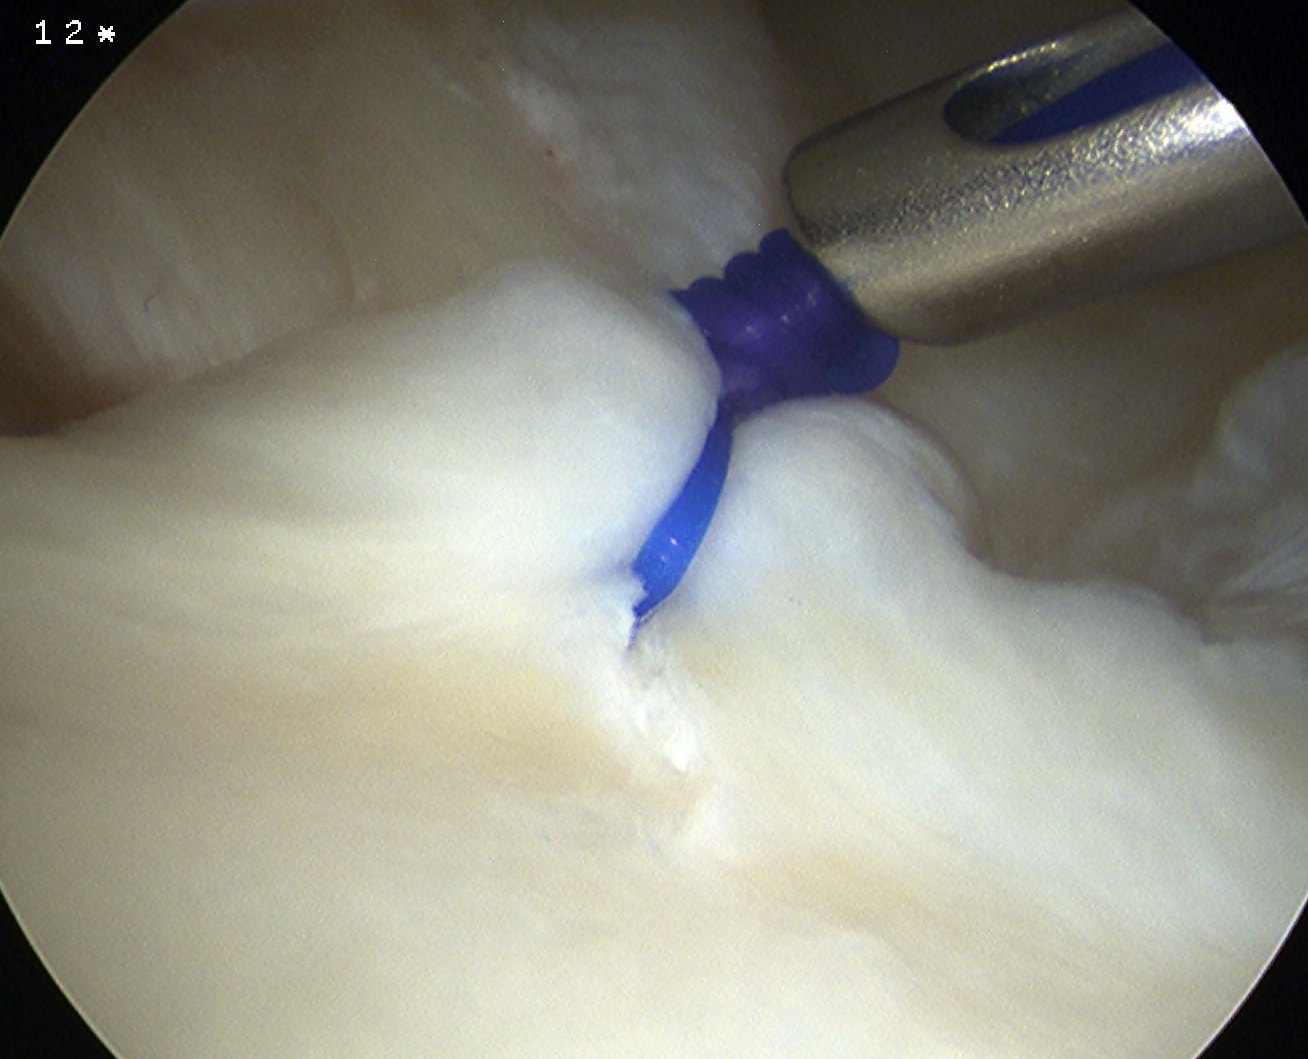

Arthroscopic capsular plication

Technique

Anterior capsular plication +/- rotator interval closure

- option 1: Suture plicate capsule to labrum

- option 2: Anchors in glenoid and use to plicate capsule to labrum

Anterior capsular plication with sutures

Anterior capsular plication with suture anchors